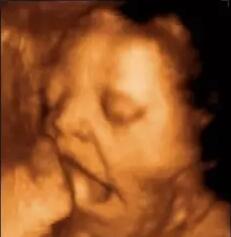

小家伙从子宫温床 降生到人间 从受精卵到可爱模样 你又惊又喜 十月怀胎,你走得不易 小家伙也没闲着哦 1、微微一笑很倾城 2、睁眼看世界 3、别吵哦,宝宝正做着美梦呢~ 4、困了,... 好新奇!宝宝在子宫里都在干嘛呢? 2016-04-16

1、筛查目的不同 普通B超可以筛查胎儿四肢和躯干部位畸形,而四维彩超能多方位、多角度、立体显示胎儿生长发育情况,为早期诊断胎儿先天性体表畸形如唇腭裂,脊柱裂,大脑、肾、... 已经做过B超,还有必要做超声影像(四维彩超)吗? 2016-04-09